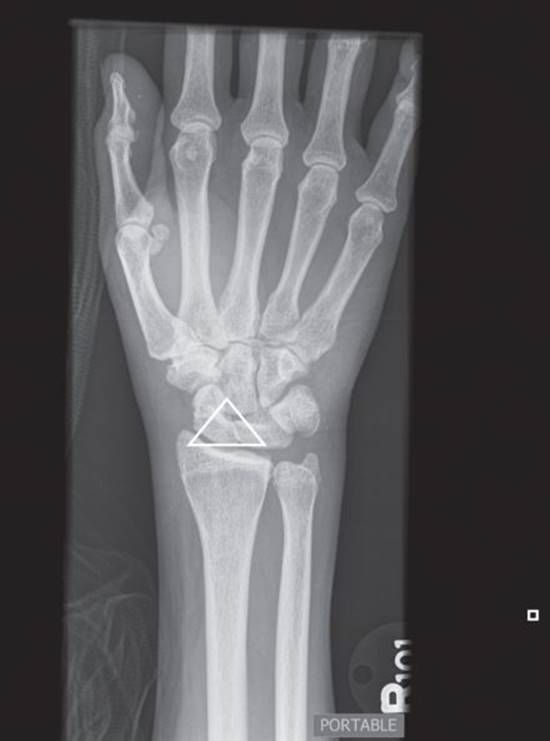

· A Colles fracture (Figures 1.1 and 1.2): A transverse fracture of the distal radial metaphysis with dorsal displacement and angulation, often caused by a fall on an outstretched hand

Figure 1.1 Colles fracture. Note the dorsal angulation of the distal radius as shown in Figure 1.2. (Image courtesy of Carl Germann, MD.)

Figure 1.2